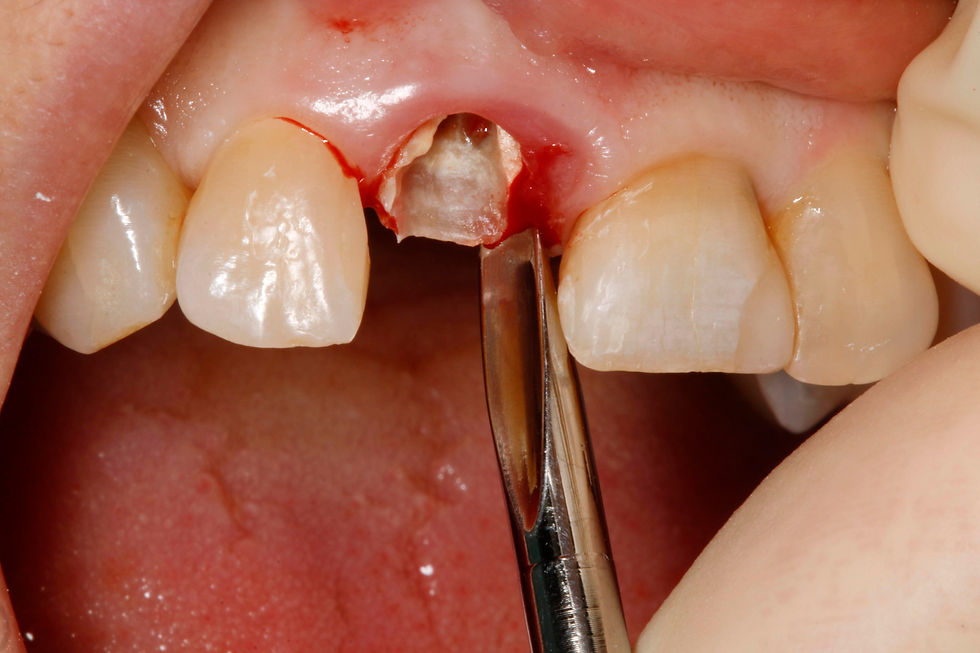

Occlusal and frontal view of the radicular residue.

The fractured element is removed in the most atraumatic way with the aid of the Magnetic Mallet.